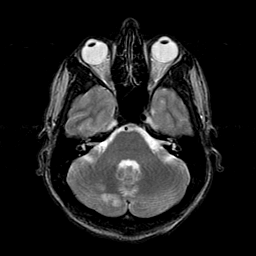

Sarcoma, MR Study #1 mr-t2 -- Slice #5

[Home][Help][Clinical] Slice 5